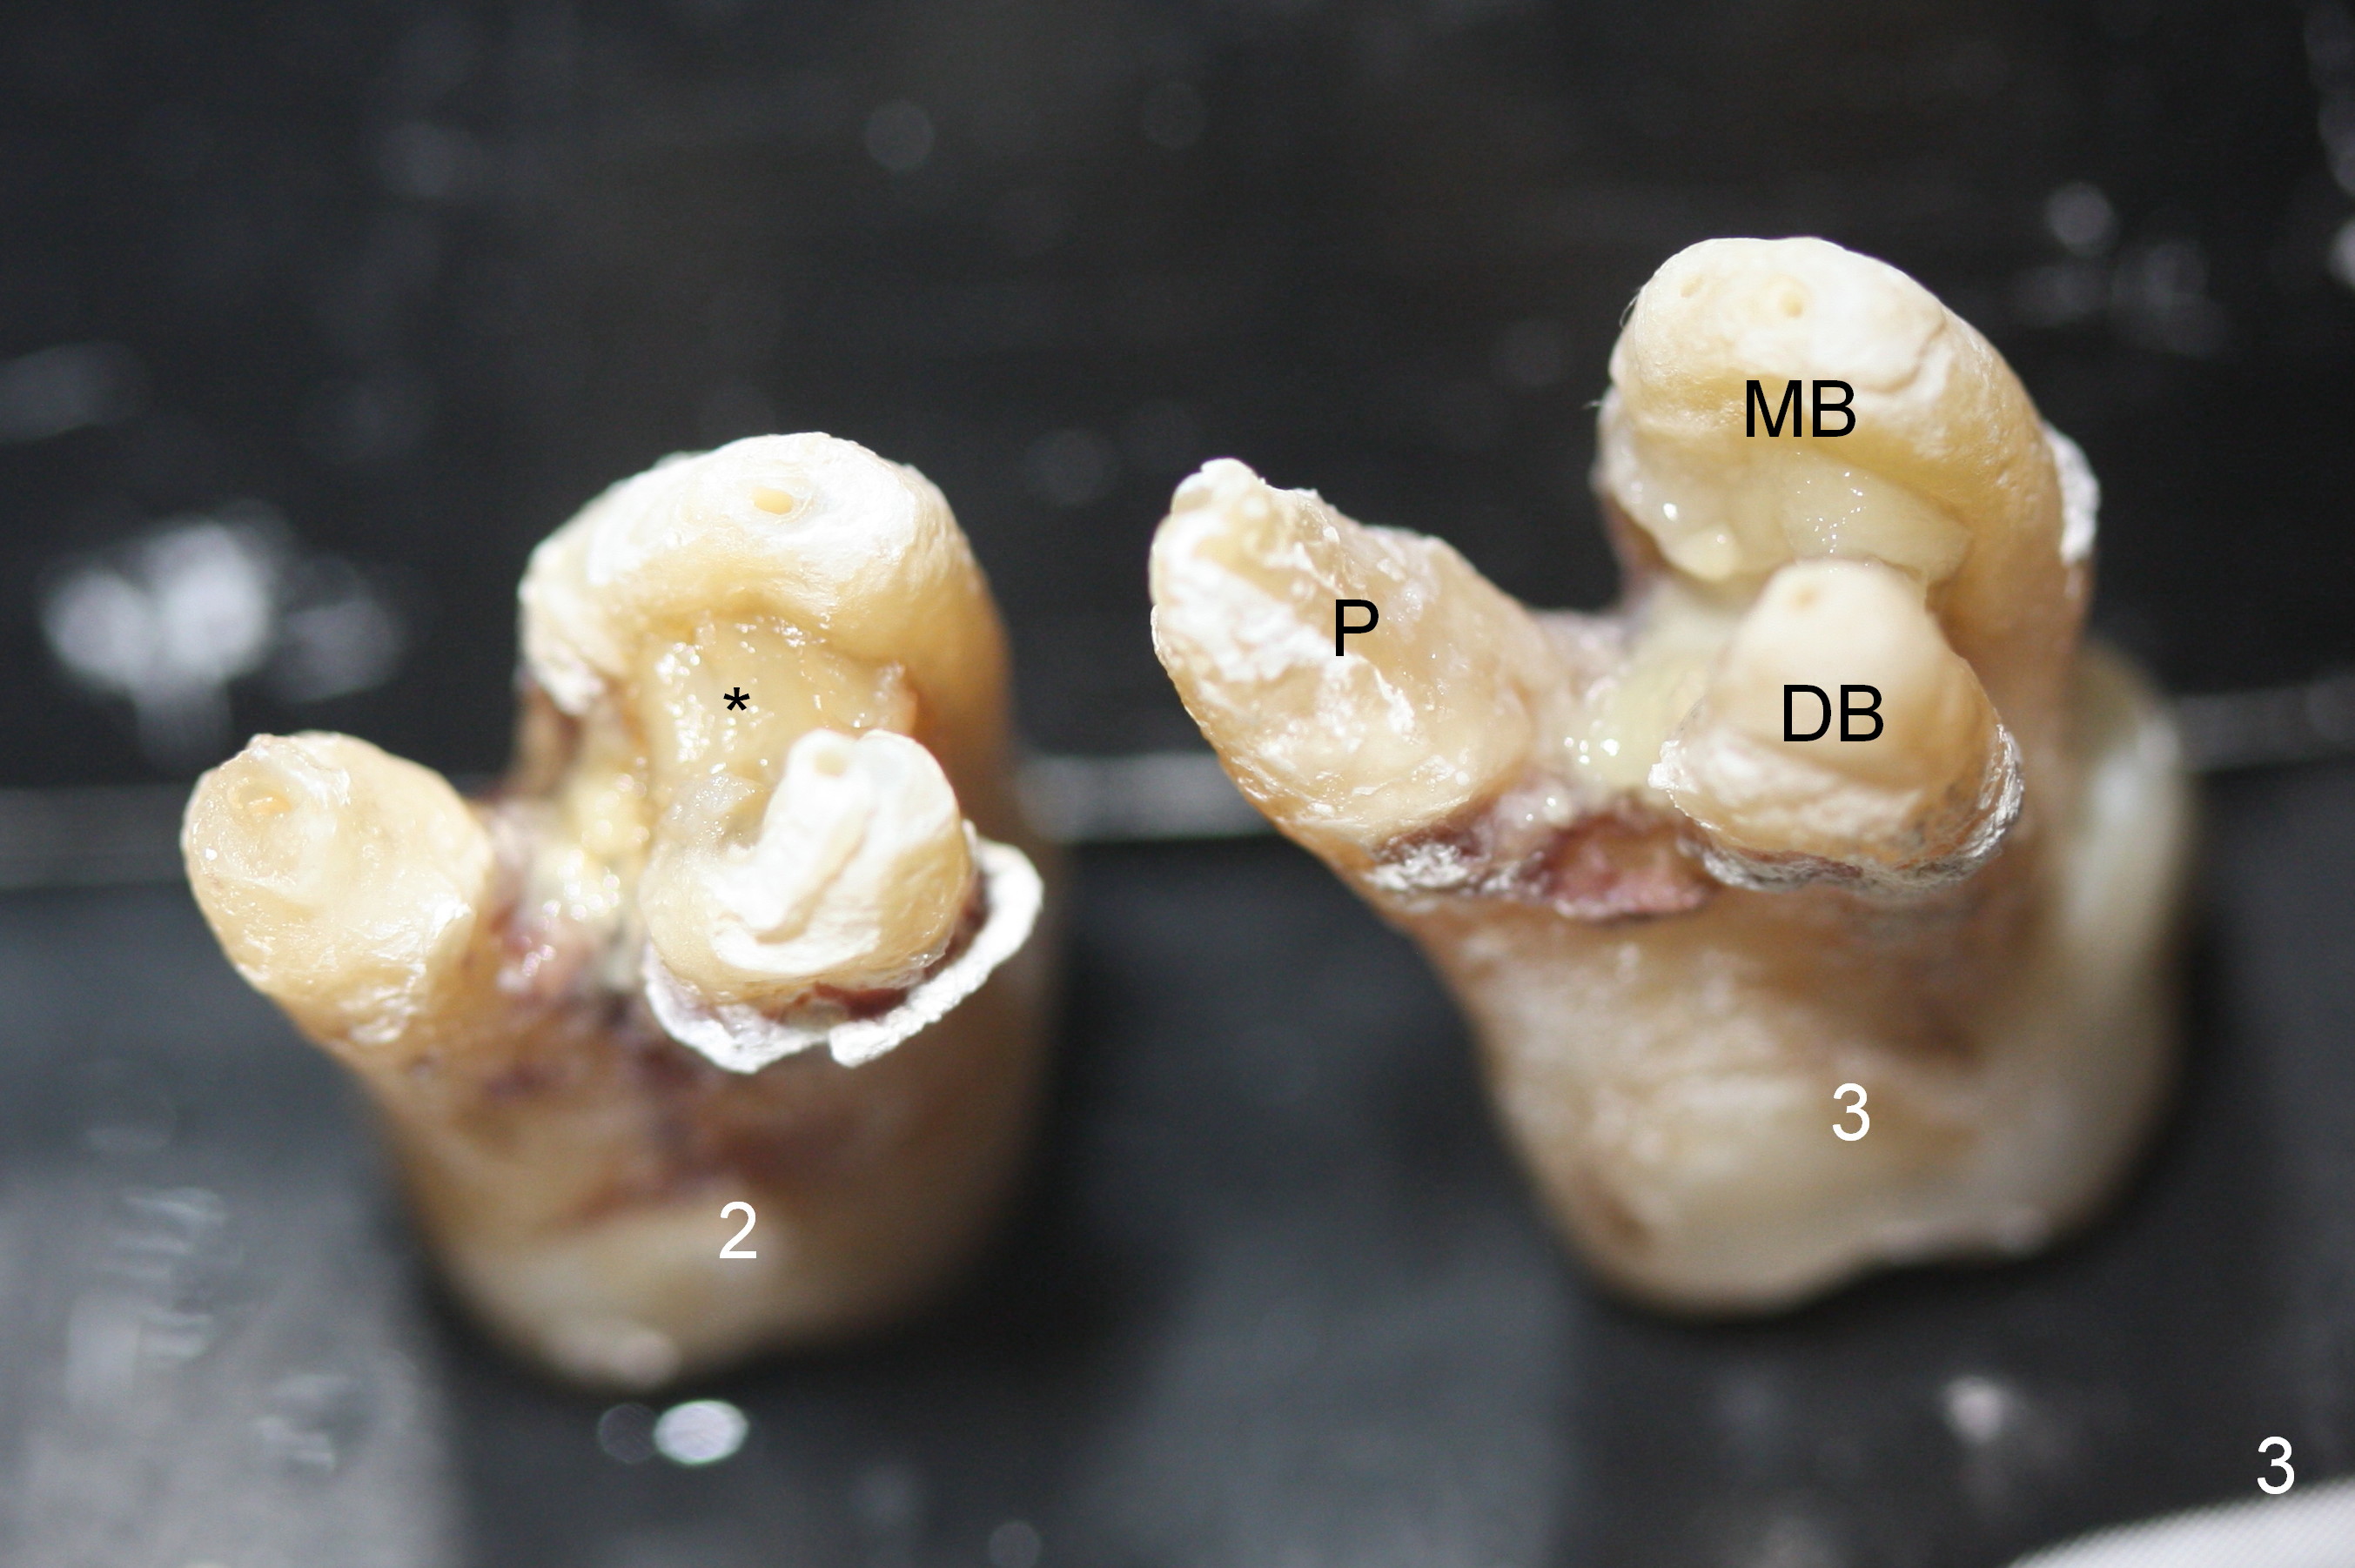

The maxillary 1st molar has 3 widely separated roots (Fig.1-3: #3) with a wide septum in between, as compared to the 2nd one (#2). The septum is a suitable site of immediate implant. When the septum is destroyed by pathology, the immediate implant has to be big.

By comparing the root morphology of an extracted tooth (Fig.7,8: #15) with that of X-ray (Fig.9) repeatedly, we can develop an ability to visualize the septum prior to surgery.